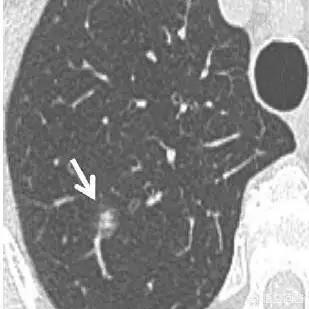

L'étape suivante consiste à déterminer la nature bénigne ou maligne des nodules pulmonaires. Les nodules bénins ne sont en aucun cas des ganglions lymphatiques dans les poumons, des tumeurs difformes, des pneumocytomes sclérosants, etc. Les nodules restants sont ceux qui peuvent être bénins ou malins, et le principe général du traitement de ces nodules est de recommander un suivi, avec un délai de révision allant de 3 mois à 1 an, en fonction des spécificités du nodule (morphologie, taille, densité, etc.). Certains nodules peuvent se résorber et disparaître au cours du suivi, comme les nodules inflammatoires, tandis que d'autres peuvent rester inchangés, comme les granulomes, ce qui est une bonne information. Si des signes de malignité apparaissent au cours du suivi, tels que l'élargissement du nodule, l'augmentation des composants réels ou solides dans le nodule de verre dépoli, un nodule plus dense, ou la présence de vaisseaux sanguins périphériques qui se développent, etc. En fait, c'est comme regarder les gens, un visage de droiture est généralement une bonne personne, une mauvaise personne féroce et vicieuse, et certains temporaires ne peuvent être vus que par l'observation du comportement de la personne, si les règles ne sont généralement pas effrayées, et si vous trouvez qu'il y a un mauvais comportement devrait être traité en temps opportun. Figure 1, nodule de verre dépoli dans la partie supérieure du poumon gauche (flèche orange), suivi pendant plus de deux ans sans changement. Figure 2, deux petits nodules de verre dépoli dans la partie supérieure du poumon droit (flèches orange), qui ont disparu après deux ans. Figure 3, nodule en verre dépoli dans la partie supérieure droite du poumon, qui a grossi au cours du troisième suivi, il est recommandé de le traiter positivement, et la pathologie chirurgicale du carcinome in situ, c'est-à-dire des lésions précancéreuses, peut réellement tuer le cancer du poumon dans l'œuf.

Il s'agit d'un cas d'adénocarcinome pulmonaire confirmé chirurgicalement.